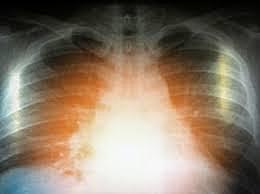

• Chest contusion

Chest contusion

I got a chest contusion during a Basketball game and it affected me a lot. I didn't know I had it. I had trouble breathing and I didn't know why which triggered my very bad anxiety and gave me many panic attacks but my parents helped me through it all and so did many doctors. This injury that I received and the experiences that came with it gave me the inspiration to become a doctor.